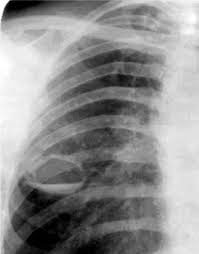

каверна на рентгенеПатологические изменения в ткани легких, сопровождающиеся воспалительным процессом, приводят к тому, что состояние пациента резко ухудшается. У него возникает симптоматика туберкулеза:

Золотым стандартом в диагностике фиброзно-кавернозного туберкулеза является рентген. На снимке можно обнаружить следующие признаки:

1. Появление каверн – полостей неправильной формы с размытыми контурами;

2. Обнаружение фиброзного перерождения ткани легких вокруг кавернозных очагов;

3. Уменьшение расстояния между ребрами, которое заметно на рентгеновском снимке;

4. Смещение органов средостения (пищевода, трахеи и других) в сторону поврежденных тканей;

5. Деформация и смещение корней легких.

При наличии острого процесса рентген поможет обнаружить новые полости некротического распада, которые по контуру окружены воспалительным процессом, также заметным на снимке.